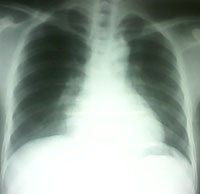

Sau 3 tuần điều trị:

-Tỉnh táo, da niêm hồng hào, không sốt, huyết động ổn định;

-Khám hô hấp, nghe phổi bình thường, tim mạch bình thường;

-X-quang phổi, siêu âm không còn dịch màng phổi.